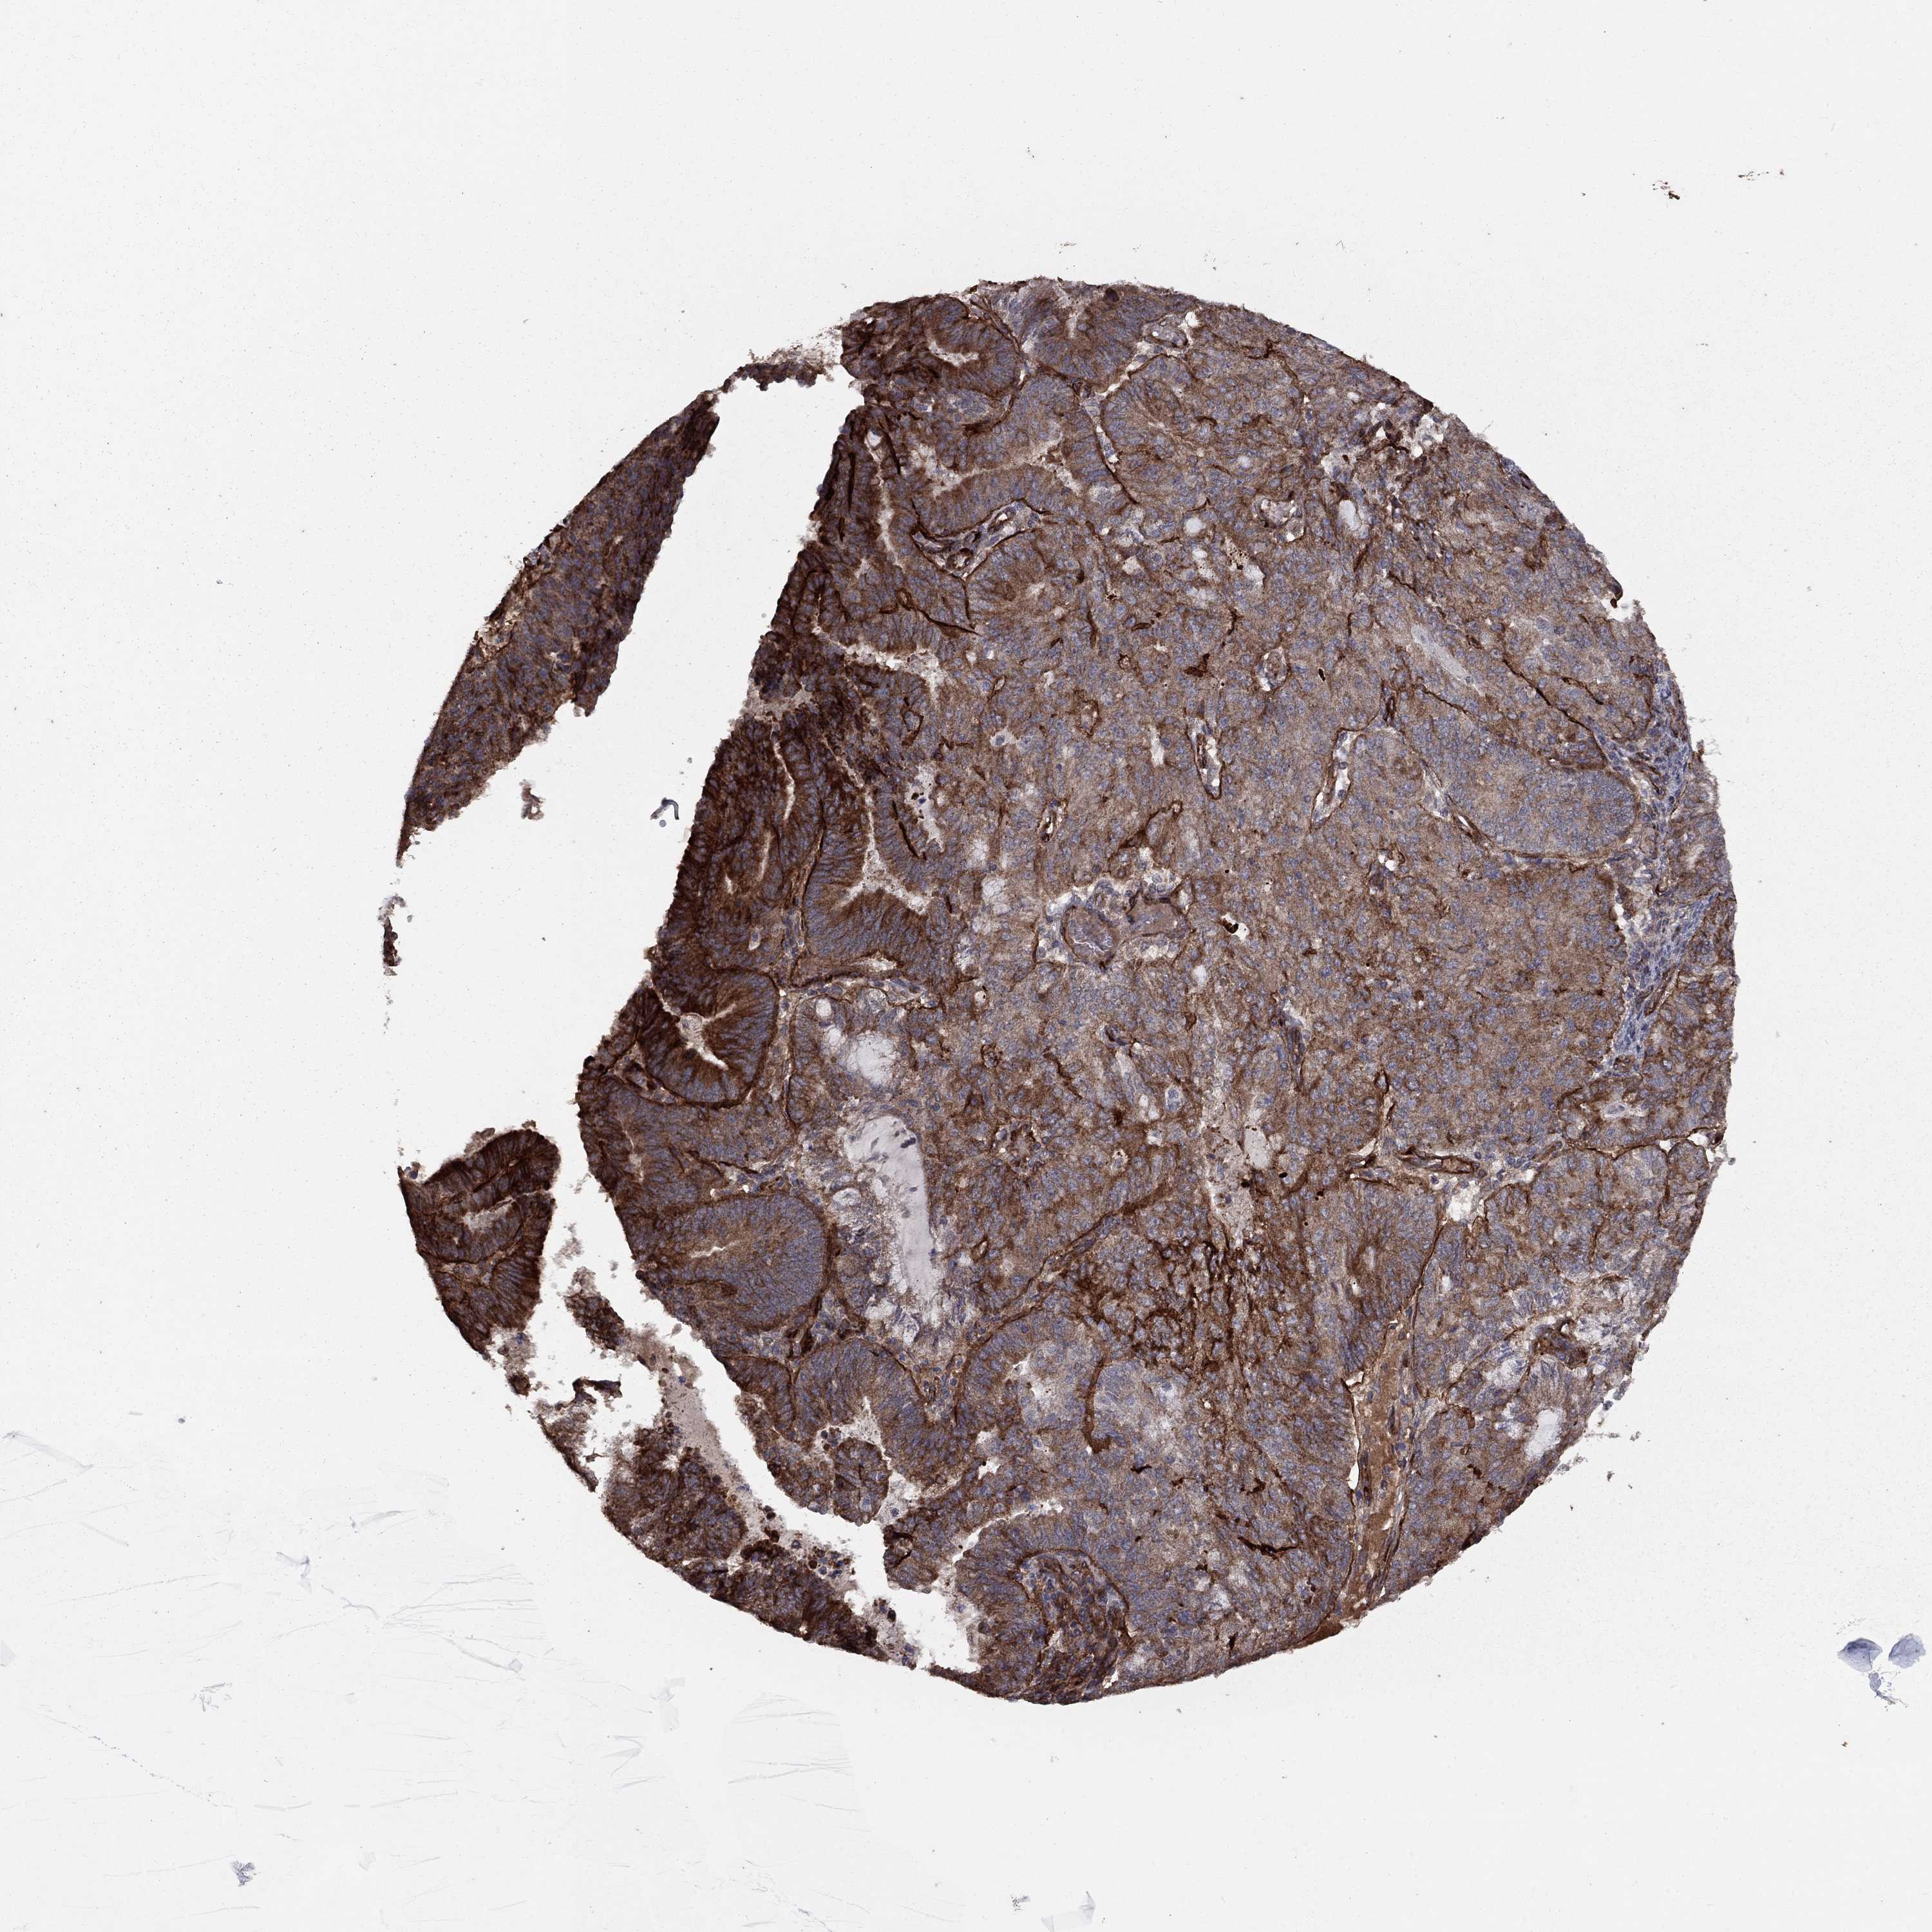

ENDOMETRIAL CANCER - Protein expressioni

A mouse-over function shows sample information and annotation data. Click on an image to view it in a full screen mode. Samples can be filtered based on level of antibody staining by selecting one or several of the following categories: high, medium, low and not detected. The assay and annotation is described here.

Note that samples used for immunohistochemistry by the Human Protein Atlas do not correspond to samples in the TCGA dataset.

Antibody stainingi

Antibody staining in the annotated cell types in the current human tissue is reported as not detected, low, medium, or high, based on conventional immunohistochemistry profiling in selected tissues. This score is based on the combination of the staining intensity and fraction of stained cells.

Each image is clickable and will lead to virtual microscopy that enables deeper exploration of all samples and also displays staining intensity scores, fraction scores and subcellular localization as well as patient and tissue information for each sample.

Antibody HPA030933

Staining

High

Medium

Low

Not detected

Intensity

Strong

Moderate

Weak

Negative

Quantity

>75%

75%-25%

<25%

None

Location

Nuclear

Cytoplasmic/membranous

Cytoplasmic/membranous,nuclear

Adenocarcinoma, NOS